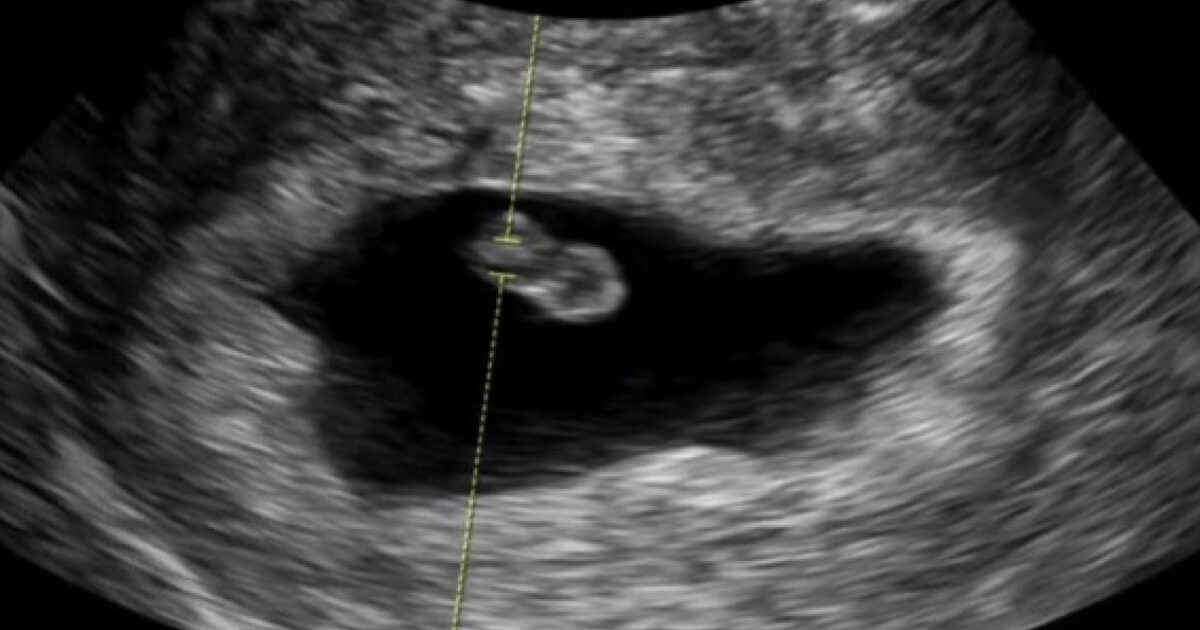

Alongside an ultrasound photo, Ayane joyfully announced, “I finally got to meet Bokboki (the nickname for the baby).” She added, “We will soon become a family of four,” expressing happiness and anticipation by adding “Bokboki” to a warm family photo.

Finally, Ayane expressed her emotional feelings, “It’s been about 8 weeks now, and Bokboki is growing well. I’m fighting morning sickness, but even that I’m thankful for.” She revealed her current severe morning sickness, saying, “It’s been about 10 days since the morning sickness started and I lost 2kg. I haven’t vomited, but I just don’t want to eat. I’m hungry but my stomach feels bad.”